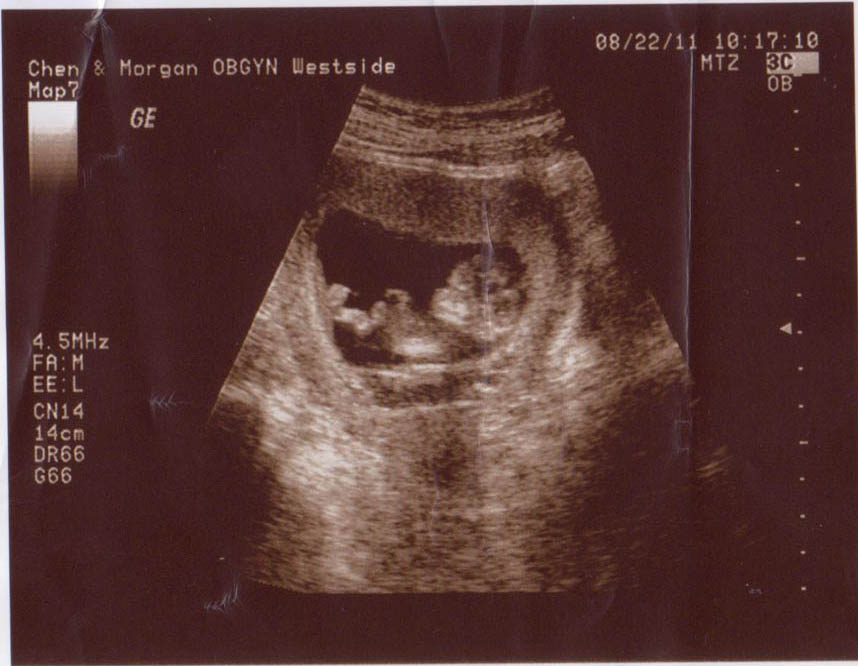

12 Weeks

11 Weeks